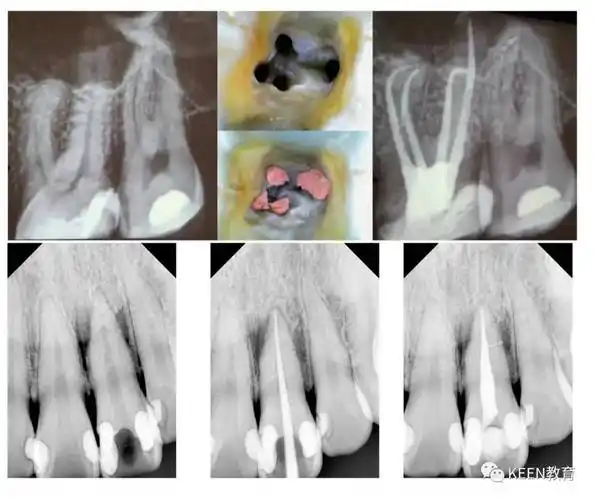

罕见的上颌第二磨牙腭侧双根管病例展示

上颌第二磨牙根管解剖形态特点及病例分享